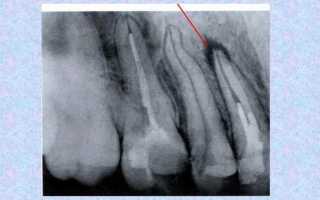

На рентгенограмме гранулема выглядит как округлая тень у верхушки корня. На поздних стадиях гранулематозного периодонтита можно увидеть участки разрушенной костной ткани с ровными контурами. Рентгенография помогает исключить другие заболевания с похожими симптомами, такие как:

При первых двух заболеваниях рентгенограмма не показывает патологических изменений в периодонте и прилегающих тканях. При фиброзном воспалении наблюдается расширение зазора между корнем и альвеолярным отростком. В случае гранулирующего периодонтита контуры зон разрушения кости размытые и рваные. Корневая киста имеет очаг разрушения кости размером более 10 миллиметров с четкими границами.

Хронический гранулирующий периодонтит 6 зуба нижней челюсти

image